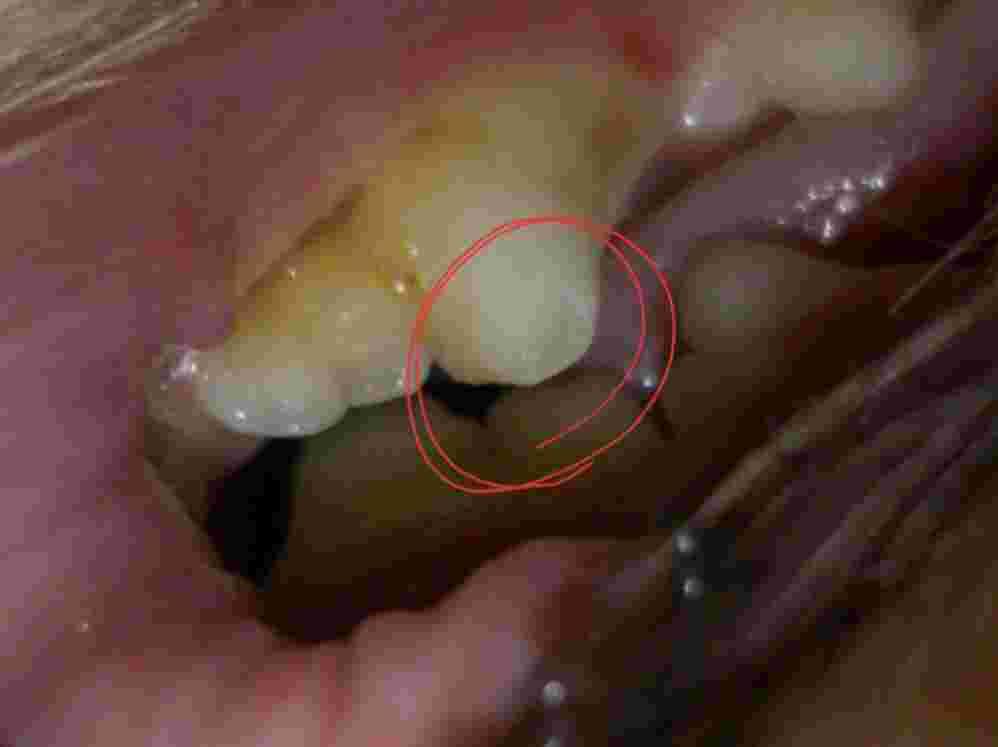

I was checking my dogs back teeth as I have been brushing them more frequently to help reduce tartar build up,because her previous owners must have never done so anyways today I thought I noticed a broken piece in her back tooth I'm not sure if it's just my over worrying but shes eating well,drink well and I touch it and she doesn't seem in any pain but again I'm no doctor. She is peeing and pooping fine too. I'm just curious as if I'm the only one seeing it

That may be a fracture tooth or an enamel defect. A close physical exam would likely be needed for confirmation of either. There doesn't appear to be any pulp exposure which is good. Monitor for decreased appetite, drooling or difficulty chewing on that side of the mouth. If you see any of these symptoms, have Harley examined by your veterinarian.